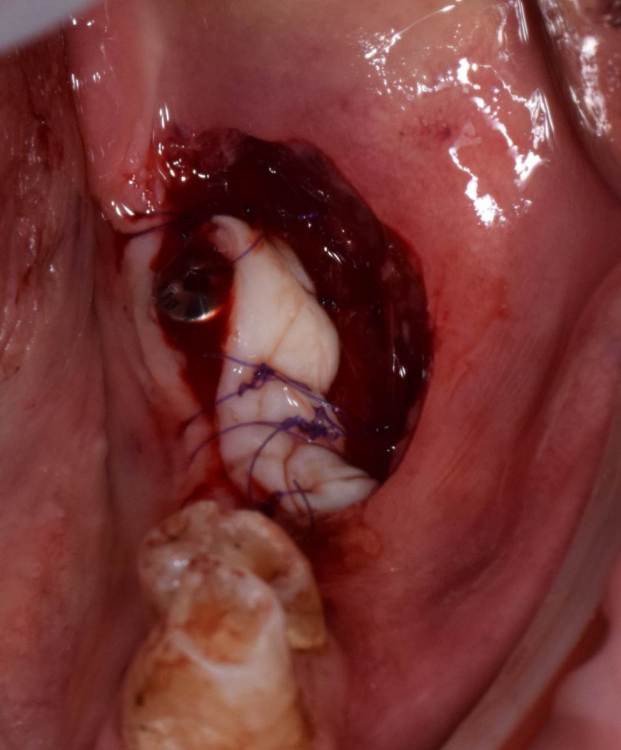

Fin Опубликовано 23 июня, 2023 Поделиться Опубликовано 23 июня, 2023 Коллеги. Подскажите какая самая частая проблема некроза СДТ. Уже много всего перепробовал. На 7 день вижу некроз. Раньше думал что очень много шью, и передавливаю. Потом думал что транспоантат очень толстый и сосуды не прорастают, но истончение СДТ не дало результата. На прошлой неделе пришил слабо, но все равно получил некроз.Вот не могу понять где проблема. Ссылка на комментарий

АнтонТЛТ Опубликовано 23 июня, 2023 Поделиться Опубликовано 23 июня, 2023 Есть фото принимающего ложа? Часть трансплантата висит в воздухе Ссылка на комментарий

АнтонТЛТ Опубликовано 23 июня, 2023 Поделиться Опубликовано 23 июня, 2023 А вообще сдт должен лежать плотно на принимающем ложе и быть неподвижным если его тыркать из стороны в сторону. 1 1 Ссылка на комментарий

Fin Опубликовано 23 июня, 2023 Поделиться Опубликовано 23 июня, 2023 29 минут назад, АнтонТЛТ сказал: Есть фото принимающего ложа? Часть трансплантата висит в воздухе В воздухе была только часть которая упиралась в ФДМ. В остальных местах на кости.Фото к сожалению нет, первые фото с новым фотоаппаратом, не разобрался ещё. 26 минут назад, АнтонТЛТ сказал: А вообще сдт должен лежать плотно на принимающем ложе и быть неподвижным если его тыркать из стороны в сторону. Да, понимаю о чем вы, как раз так и стараюсь делать, проверяю.Имею большое желание попробовать пинами фиксировать. Ссылка на комментарий

kuziy12 Опубликовано 23 июня, 2023 Поделиться Опубликовано 23 июня, 2023 1 час назад, Fin сказал: В воздухе была только часть которая упиралась в ФДМ. В остальных местах на кости.Фото к сожалению нет, первые фото с новым фотоаппаратом, не разобрался ещё. Да, понимаю о чем вы, как раз так и стараюсь делать, проверяю.Имею большое желание попробовать пинами фиксировать. Посмотрите в ютюбе, есть конгресс Едранова. Он фиксирует к голой кости пинами, отслоив даже надкостницу. Я попробовал так сделать - все приросло идеально. Купите осциллирующий наконечник. Это офигенная штука в работе. Ссылка на комментарий

Fin Опубликовано 23 июня, 2023 Поделиться Опубликовано 23 июня, 2023 (изменено) 9 минут назад, kuziy12 сказал: Посмотрите в ютюбе, есть конгресс Едранова. Он фиксирует к голой кости пинами, отслоив даже надкостницу. Я попробовал так сделать - все приросло идеально. Купите осциллирующий наконечник. Это офигенная штука в работе. Осциллирующий наконечник есть правда Kavo, покупал как раз для этой цели, но его смотрю не очень хвалят. Про технику Едранова тоже слышал на конгрессе в 20 году, очень понравилась но пока не пробовал Вы тоже к кости фиксировали? Изменено 23 июня, 2023 пользователем Fin Ссылка на комментарий

kuziy12 Опубликовано 24 июня, 2023 Поделиться Опубликовано 24 июня, 2023 Да. Забрал лоскут с неба и припинил прямо к кости. Все должно быть плотно, неподвижно. Гораздо быстрее и удобнее, чем швами фиксировать Ссылка на комментарий